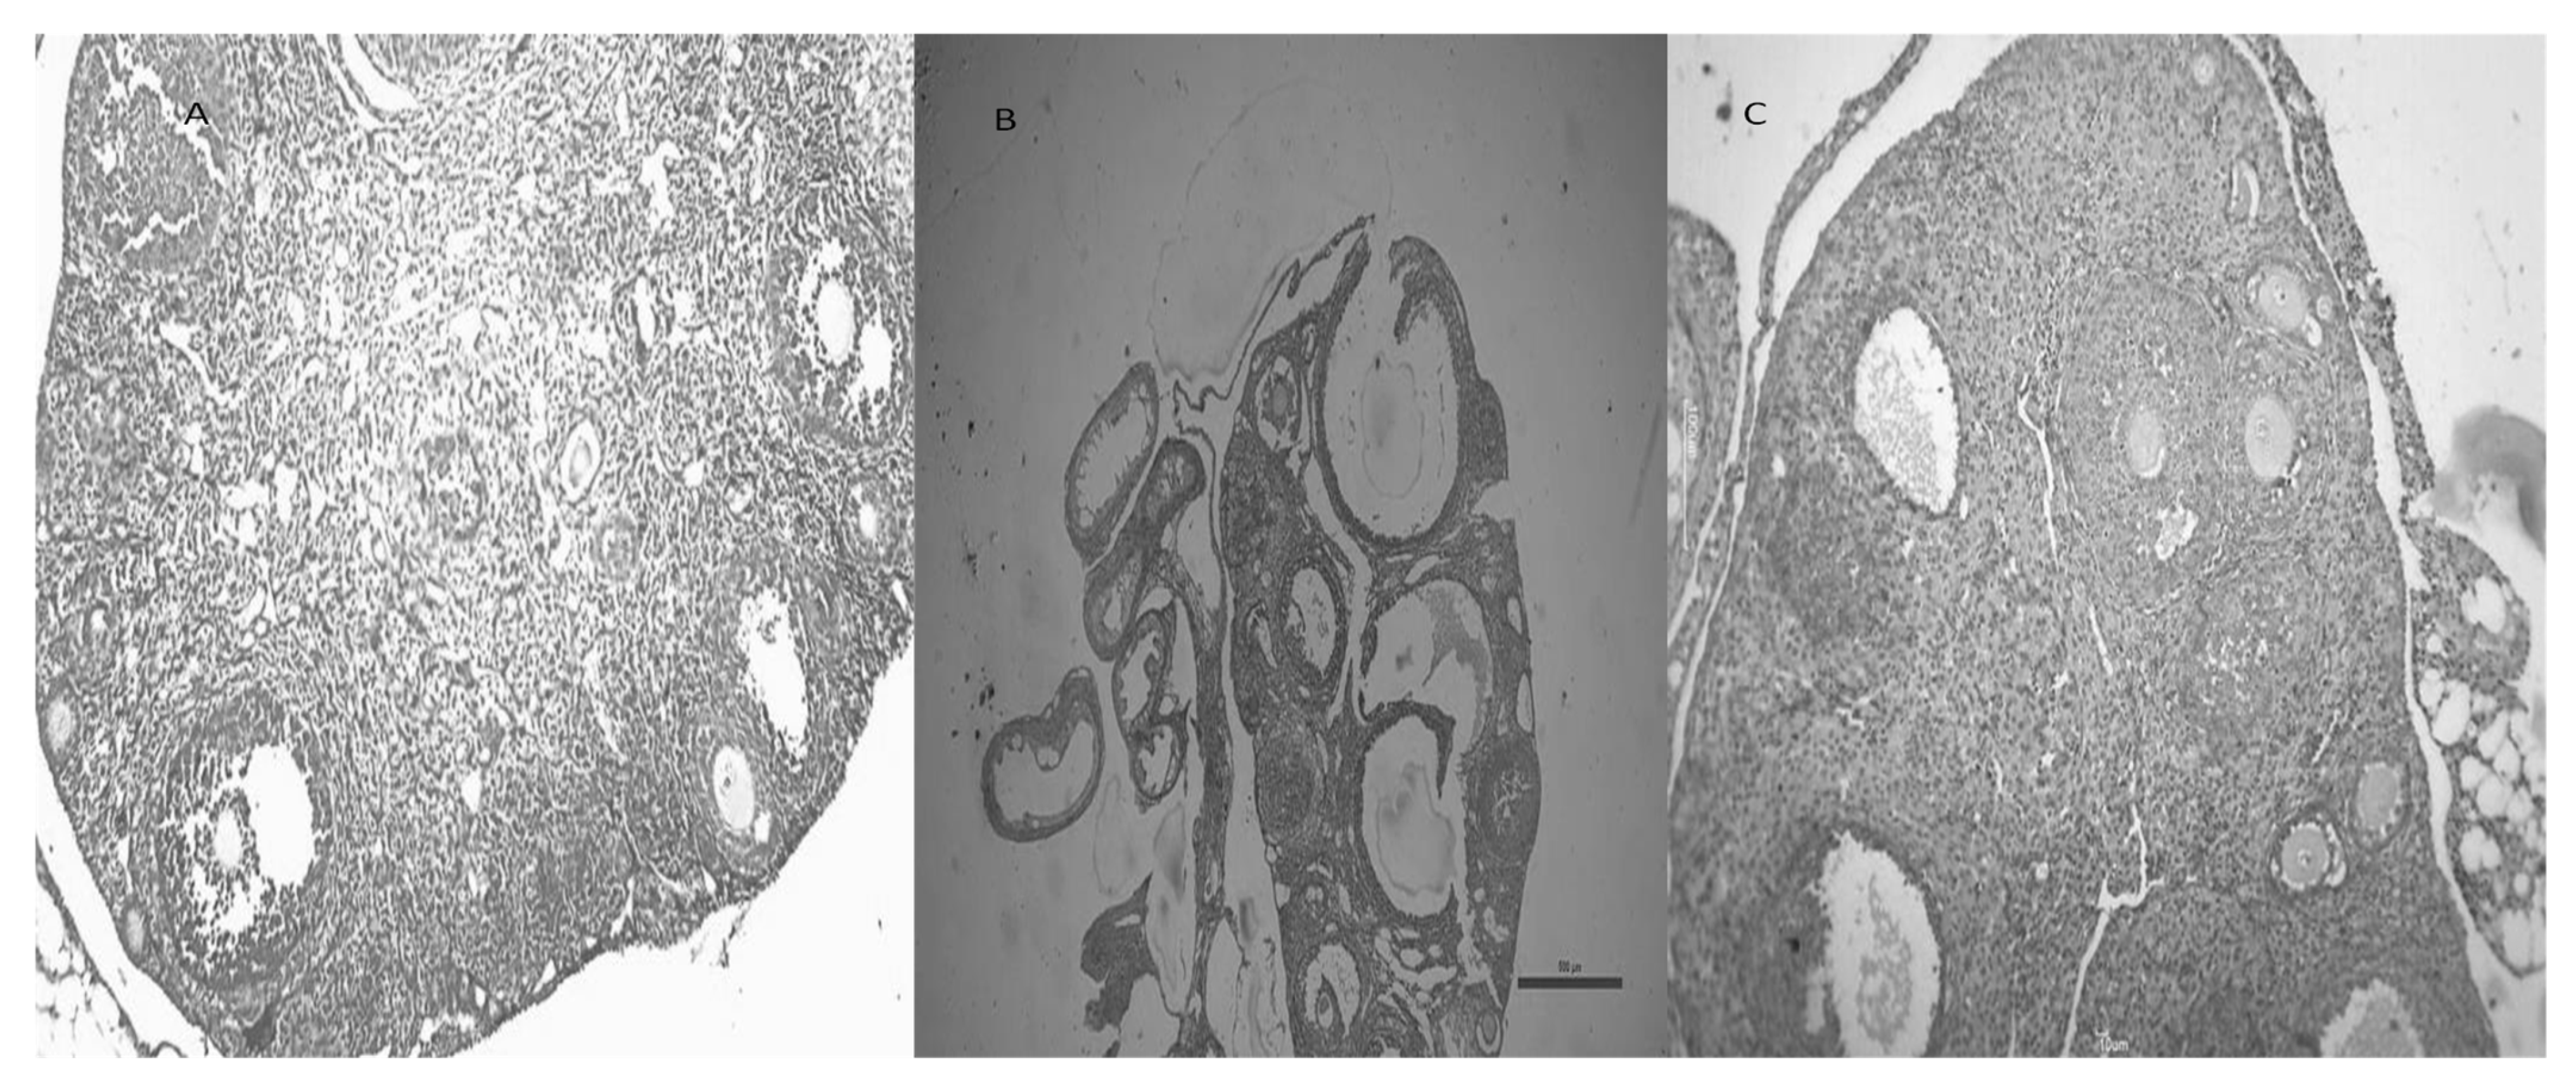

3.9. CGA Improves Ovarian Morphology in Mice with Letrozole-Induced PCOS